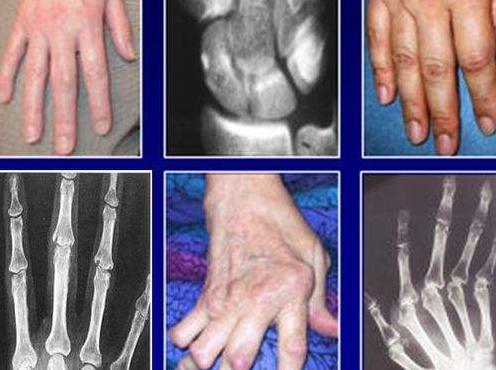

類風(fēng)濕性關(guān)節(jié)炎具有隱匿性高、難確診、受損不可逆和致殘率高等特點(diǎn)。它可以發(fā)病于身體的任何一個(gè)關(guān)節(jié),常發(fā)病于指、掌、腕部小關(guān)節(jié)。

據(jù)調(diào)查研究表明,隱匿型類風(fēng)濕性關(guān)節(jié)炎患者占類風(fēng)濕關(guān)節(jié)炎病人總數(shù)的60-70%。緩慢起病,常于數(shù)周或數(shù)月內(nèi)逐漸起病,表現(xiàn)為掌指關(guān)節(jié)和腕關(guān)節(jié)的疼痛、腫脹和僵硬,可伴全身不適和乏力、低熱、食欲不振、體重下降等。

2、經(jīng)過(guò)數(shù)周或數(shù)月后出現(xiàn)關(guān)節(jié)疼痛、腫脹,往往從一個(gè)或幾個(gè)關(guān)節(jié)受累,常首先累及大關(guān)節(jié),在一段時(shí)間內(nèi)病變局限于該關(guān)節(jié),逐漸發(fā)展到數(shù)個(gè)、十幾個(gè)或數(shù)十個(gè)關(guān)節(jié)受累,終可擴(kuò)散到腕、指、踝、趾等多個(gè)關(guān)節(jié),呈兩則肢體關(guān)節(jié)的對(duì)稱性分布。